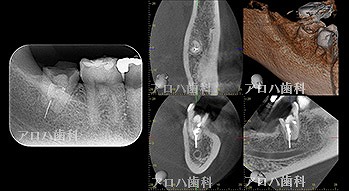

case4

再根管治療 2年予後

再根管治療の汚染の改善

破折器具除去もあり。

case5

左>頬側よりGP挿入。MB根尖の透過像と一致。P根にも透過像。穿孔を疑う。右>術後1年

左>術前

右>術後1年。

頬側の瘻孔